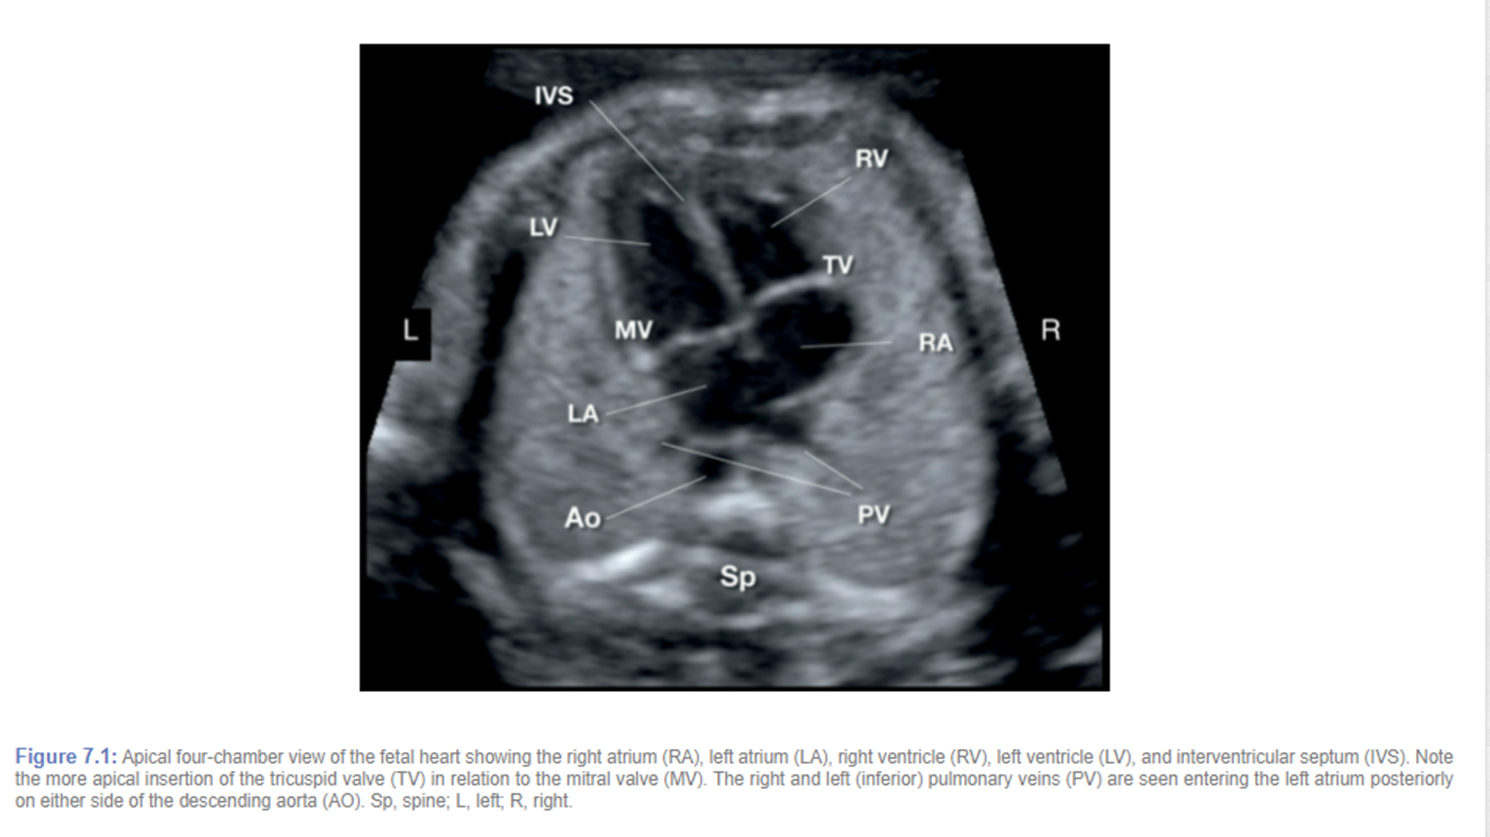

normally what is closest to anterior abdominal wall

right ventricle

what is closest to spine

left atrium

blood flow through foramen ovale

right to left

where is moderator band located

tricuspid valve on ____ side

right

mitral valve on ____ side

left

4 chamber heart should sit at a ___ degree angle and take up about ____ of the chest

45 degree

1/3

___ of the herat located in left chest with apex pointing ____

2/3

pulmonary veins drain into

there are 4 but we usually see 2

tricuspid valve is slightly displaced _____ vs mitral valve

apically